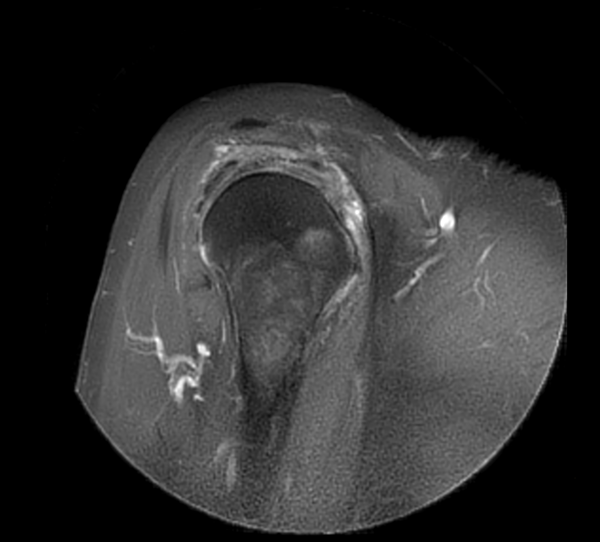

Axial MultiVane XD - PDw SPAIR